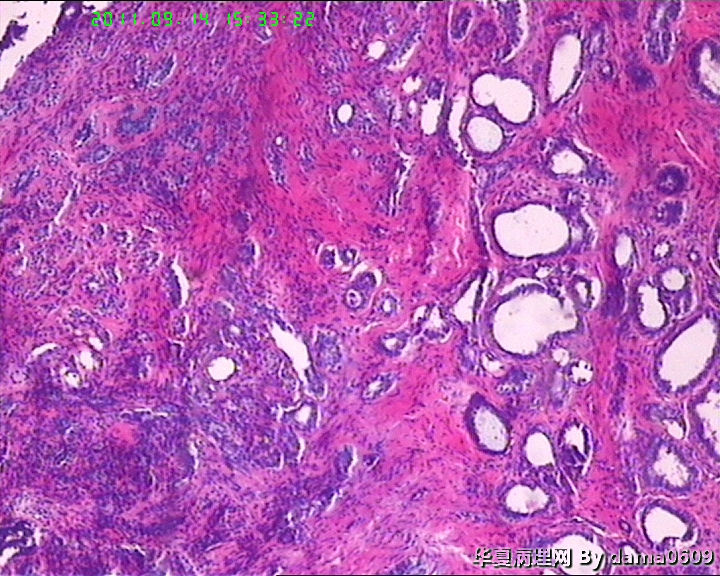

女,22岁,乳腺肿物,病史不详。

不整形软组织肿物一个,V:2.0x1.5x1.5cm。无包膜。切面实性,灰白色,小结节状,质中。

镜下结构复杂,图3、4、8、10、11、12、13、15、17、18、19、20为肿物中央区域,占标本大部分,图1、2、7、14为肿物边缘部分,图5、6、9、16、21为二者交界处。有点乱,不好意思,请老师别介意。

请教老师,诊断:硬化性腺病,可以吗??谢谢!!

会诊结果::(乳腺)腺管腺病,伴纤维腺瘤形成。

该例患者经上级医院会诊,回报:(乳腺)腺管腺病,伴纤维腺瘤形成。